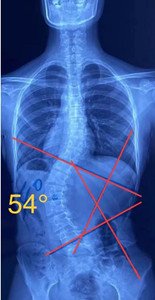

單向側(cè)彎

如果是單向側(cè)彎的患者,(腰彎或者胸彎),躺在床上,應(yīng)向患側(cè)處進(jìn)行臥位,側(cè)臥在你彎弧的凹側(cè),讓它下墜打開(kāi)。